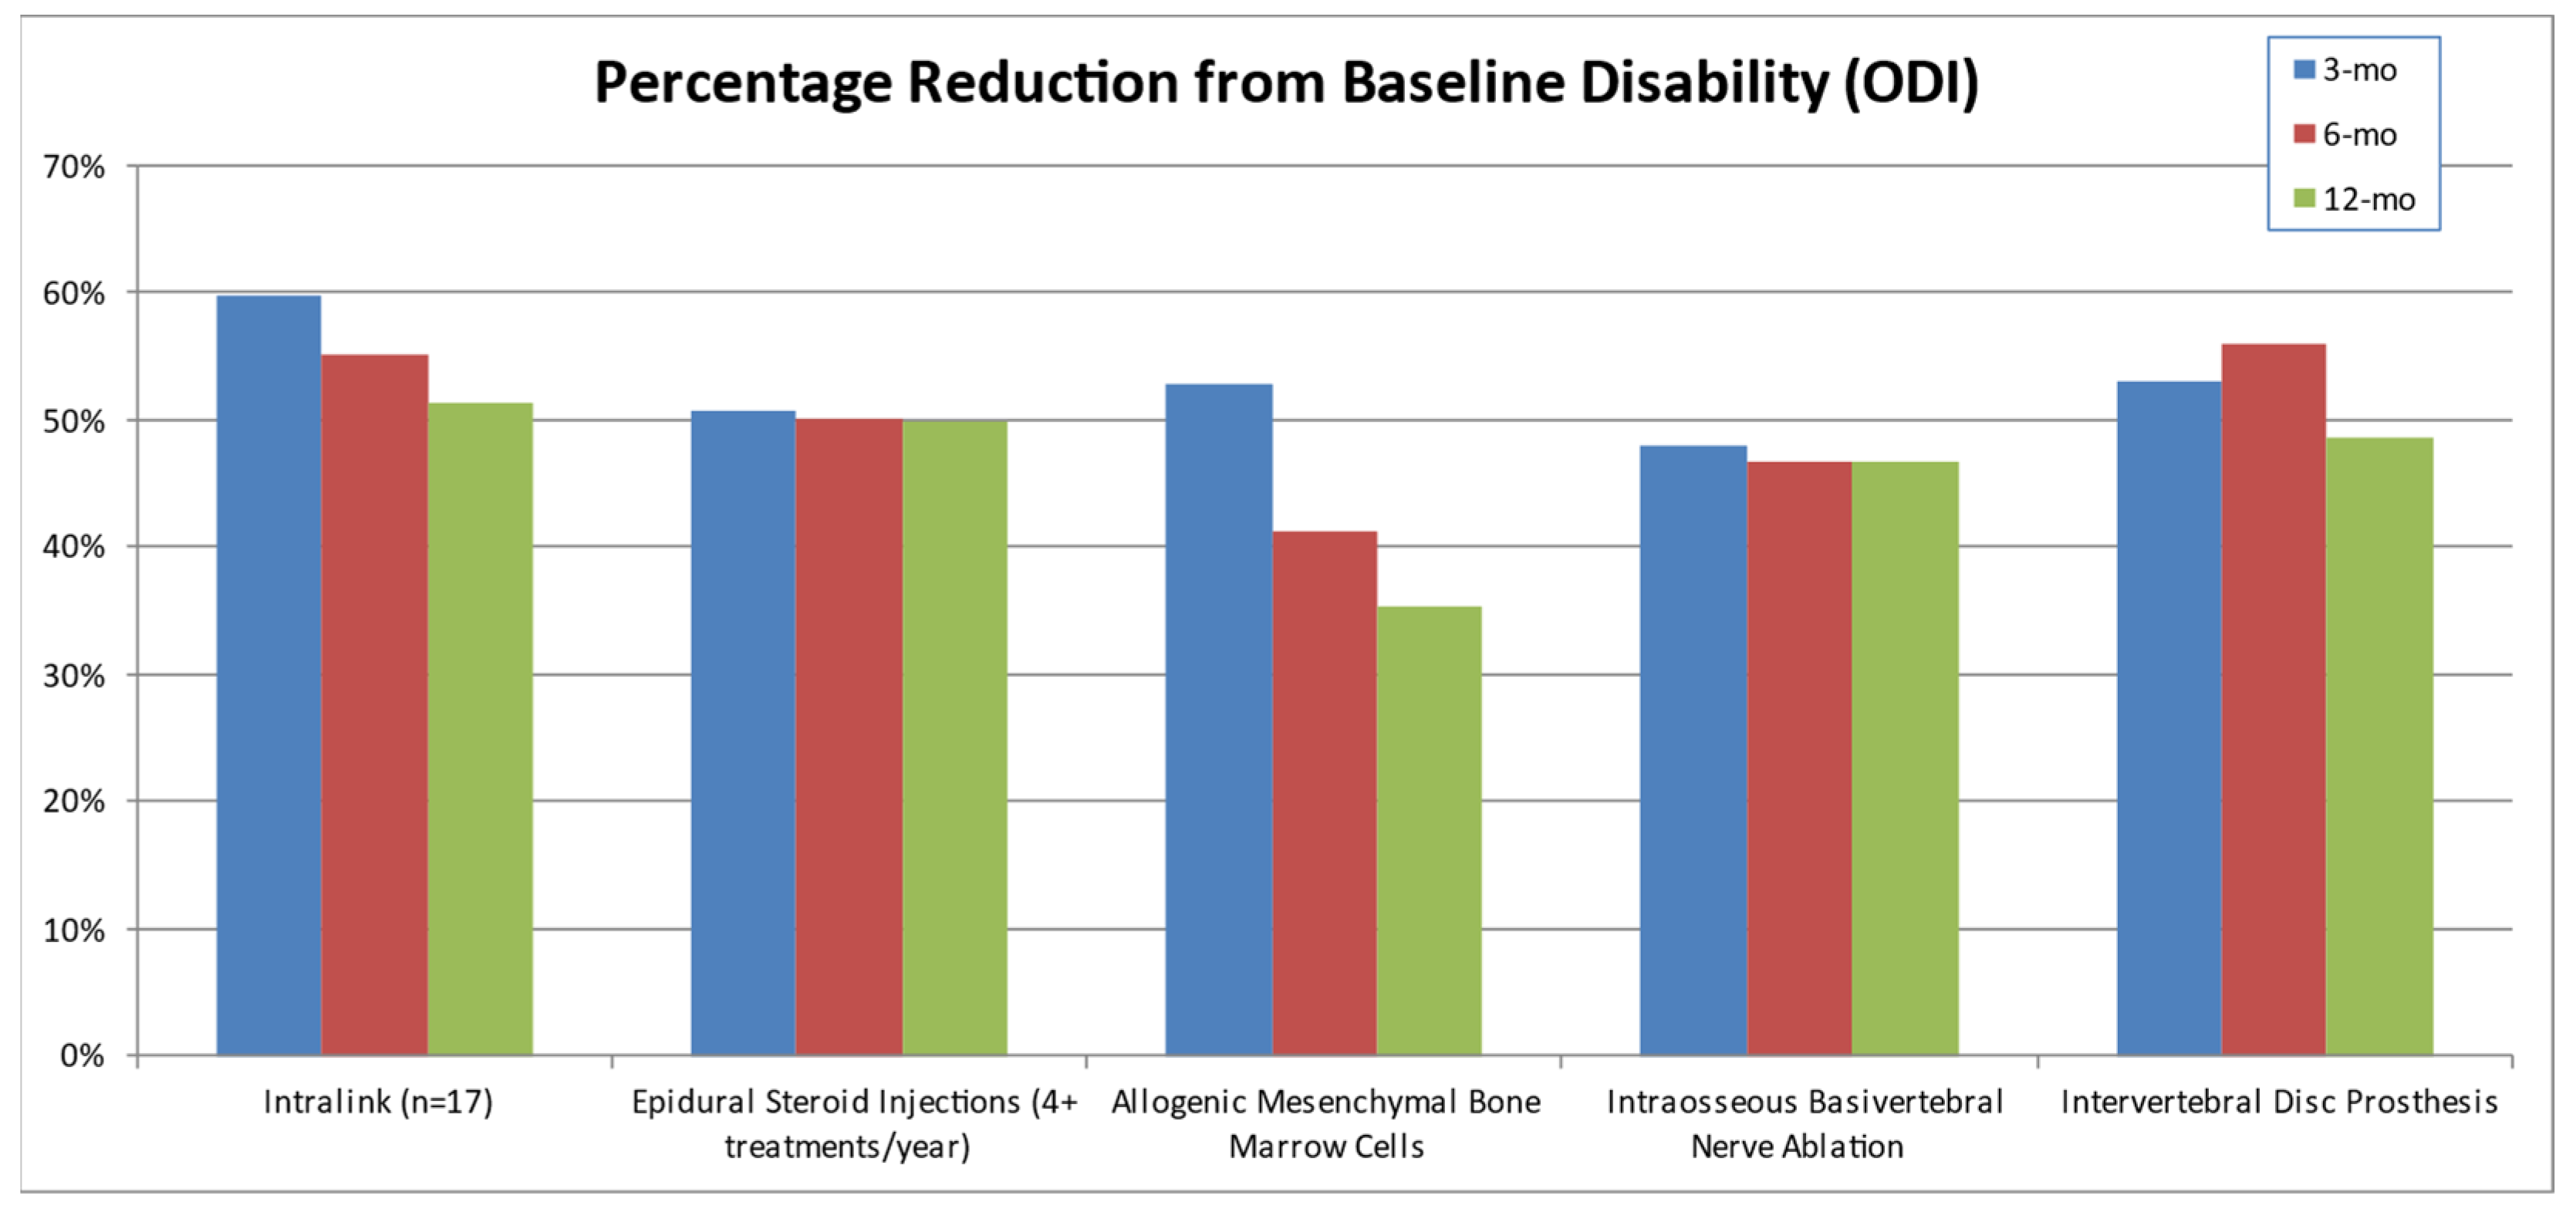

3.4. Clinical Studies Review

3.5. The Current Continuum of Care for Discogenic LBP